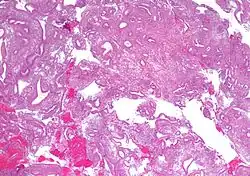

- Atypical endometrial hyperplasia (simple or complex) - Simple or complex architectural changes, with worrisome (atypical) changes in gland cells, including cell stratification, tufting, loss of nuclear polarity, enlarged nuclei, and an increase in mitotic activity. These changes are similar to those seen in true cancer cells, but atypical hyperplasia does not show invasion into the connective tissues, the defining characteristic of cancer. The previously mentioned study found that 22% of patients with atypical hyperplasia eventually developed cancer.[7]